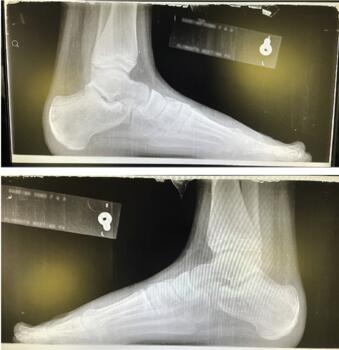

Next, it is critical to perform an appropriate radiographic evaluation, and to do so bilaterally. Assessing the growth plates with a unilateral film and no contralateral comparison may lead to misdiagnosis. Avulsion fracture in untreated Sever’s is a possibility.12 Rachel and team also reported abnormal radiographic findings in 5.1 percent of children with Sever’s leading to more aggressive treatment.13 They felt that without taking images, clinicians could miss lesions requiring more advanced treatment. Taking weight-bearing lateral images allows for evaluation of the calcaneus and a comparison of the two posterior growth plates for continuity and for advancement of closure. Evaluating for bone density, secondary ossification center, and fragmentation are also important.14 One should assess the widths of the growth plates should for possible increased separation or asymmetry, and the use of measuring options, now found on most computer radiography programs, can be helpful.

A dorsoplantar radiographic view can help determine foot type and position, especially at the talonavicular joint. I also utilize a calcaneal axial view with my pediatric patients, and due to their smaller stature, assessment of the hindfoot alignment is possible in this view as well. It is important to remember when treating the pediatric patient that you are treating not just the child, but the parents as well, and performing an X-ray does allow for additional peace of mind for the family.